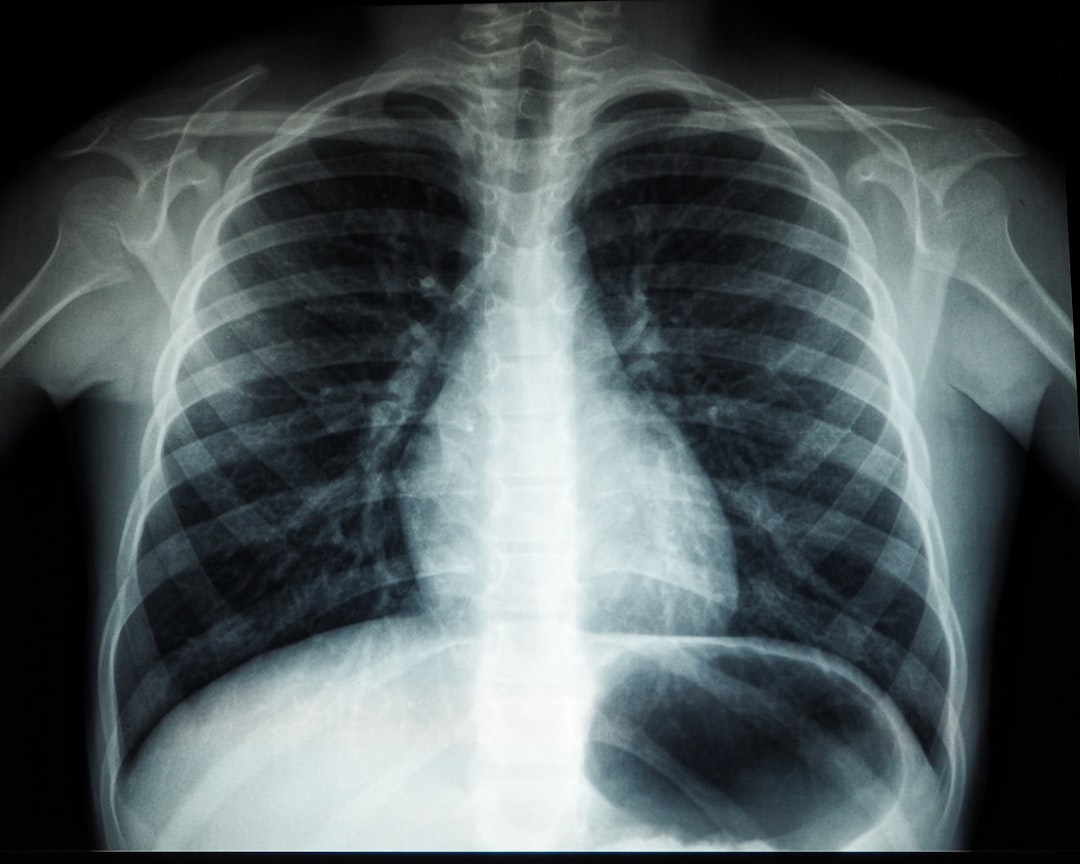

폐렴 감염 초기 열과 기침 증상은 종종 일반 감기와 혼동될 수 있습니다. 하지만, 실제로 폐렴은 좀 더 심각한 질병입니다. 폐렴은 호흡계의 염증으로 인해 발생하며, 세균, 바이러스, 또는 곰팡이에 의해서도 발생할 수 있습니다. 초기 증상으로는 발열, 기침, 가슴 통증이 있습니다. 폐렴 감염 초기 열과 기침을 경험할 경우, 즉시 전문가의 진단을 받는 것이 중요합니다.